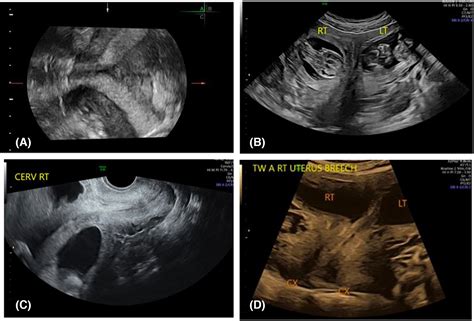

Diagnosing a Bicornuate Uterus

Diagnosing a bicornuate uterus typically involves a combination of imaging techniques. The most common methods include:

• Ultrasound: A transvaginal ultrasound can provide detailed images of the uterus and help identify any structural abnormalities.

• Magnetic Resonance Imaging (MRI): MRI provides high-resolution images of the uterus and can offer a more detailed view of the uterine structure.

• Malpresentation: The baby may be in a breech or transverse position, which can complicate delivery.